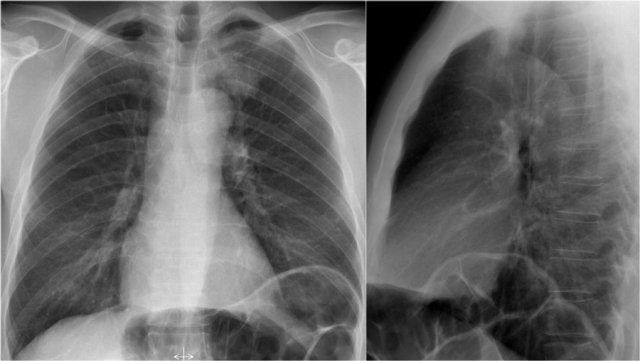

Lateral view

On a normal lateral view the contours of the heart are visible and the IVC is seen entering the right atrium.

The retrosternal space contains air and should be radiolucent down to the level where the right ventricle borders the sternum (small black arrow).

Any radiopacity in this upper retrosternal area is suspective of a process in the anterior mediastinum or upper lobes of the lungs.

As you go from superior to inferior over the vertebral bodies they should get darker, because usually there will be less soft tissue and more radiolucent lung tissue (white arrow).

If this area becomes more dense, look carefully for pathology in the lower lobes.

Diaphragm

The contours of the left and right diaphragm should be visible.

The right diaphragm should be visible all the way to the anterior chest wall (red arrow).

Actually we see the interface between the air in the lungs and the soft tissue structures in the abdomen.

The left diaphragm can only be seen to a point where it borders the heart (blue arrow).

At that point the interface is lost, since the heart has the same density as the structures below the diaphragm.